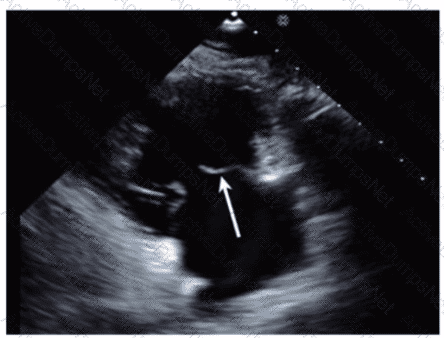

Which wall is indicated by the arrow on this image?